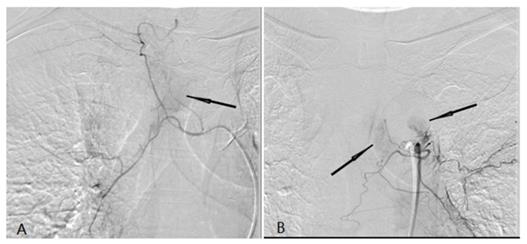

Fig 2

A tumor feeding artery derived from the right tracheal artery and there was abnormal tumor staining (black arrow) (A). (b) A tumor feeding artery derived from the left tracheal artery and there was abnormal tumor staining (black arrow) (B).

J Cancer Image